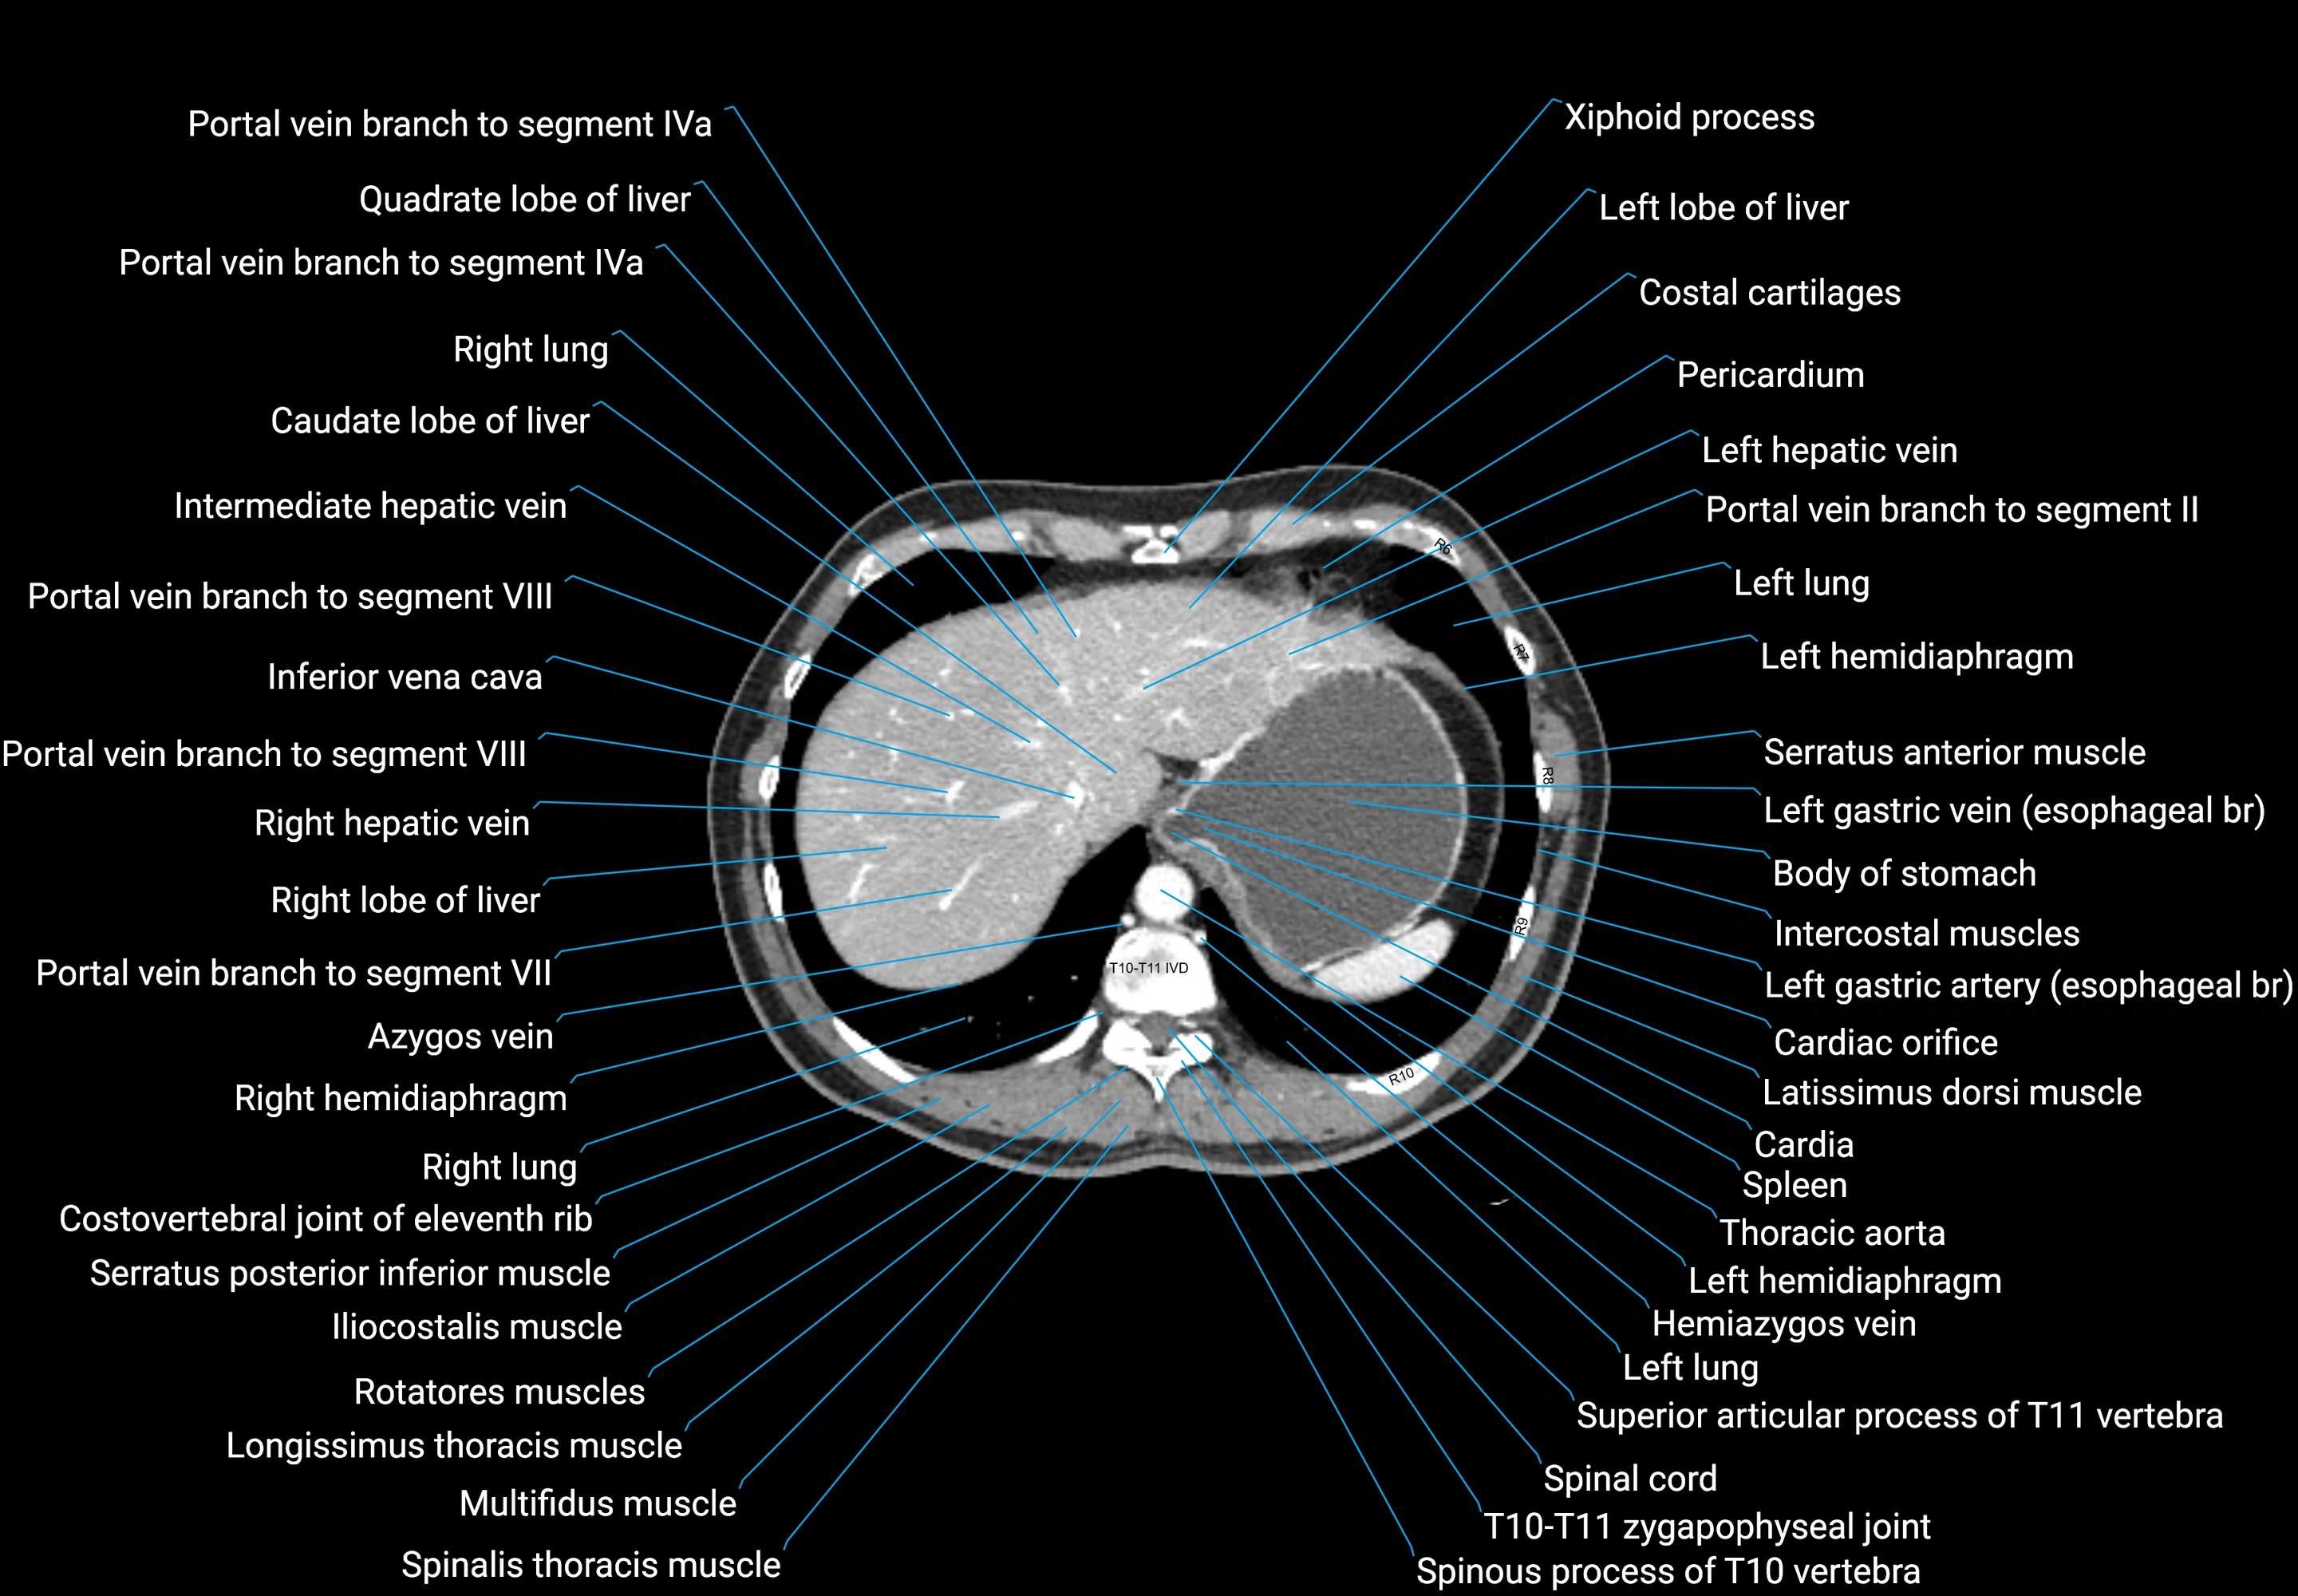

CT images